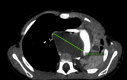

A bronchogenic cyst masquerading as asthma: A case report

Wheezing in infants and under-five children may present a diagnostic problem as there are various aetiologies for this symptom. Diagnosis of asthma is often made as it is one of the causes of wheezing in children. It is however important to have taken a complete history, including allergy and appropriate diagnostic investigations. If the child's symptoms do not improve despite appropriate therapy, a different diagnosis must be pursued. We report the case of a child who presented to us with wheezing and who did not respond to therapy.